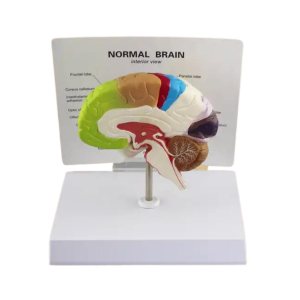

- Kadın Pelvik Taban Anatomisi: Kadın Pelvik Taban Maketi Model 38, kadın üreme sistemi, pelvik kaslar ve pelvik taban yapıları hakkında bir anlayış sağlar. Bu model, pelvik kasların yerini, fonksiyonlarını ve mevcut olan detaylı bir şekilde gösterir. Gerçekçi anatomi ve ayrıntılı tasarım , eğitim ve klinik kullanımlar için mükemmel bir araçtır.

- Gerçekçi Tasarım ve Ayrılabilir Parçalar: Modeldeki pelvik taban yapıları, yapının ayrıntılarıyla hazırlanmış olup, daha iyi görülebilmesi için genel ve ayrıntılı incelenebilir parçalar içerir. Bu sayede kadın pelvik yapıları hakkında bir eğitim sağlandı. Pelvik kasları ve organları doğru bir şekilde birleştirme ve yerleştirmelerini oldukça basittir.